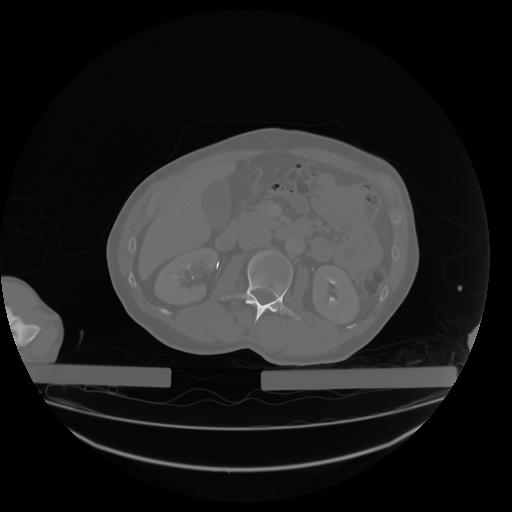

27 CUERPO,CE,Axial,3.0,CUERPO,,